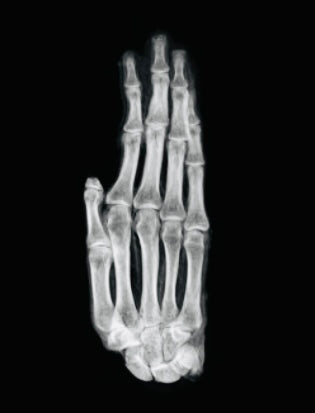

Authentification : vérification par ADN et radiographie effectuée par le laboratoire d’ADN paléo de l’Université Lakehead

Entièrement authentifié par une analyse indépendante d'ADN et de rayons X au Laboratoire d'ADN paléo (Université Lakehead) , ce spécimen est accompagné d'une documentation scientifique complète attestant de son origine ancienne et de son intégrité de conservation.

Vérifié par des tests ADN et l'imagerie radiographique